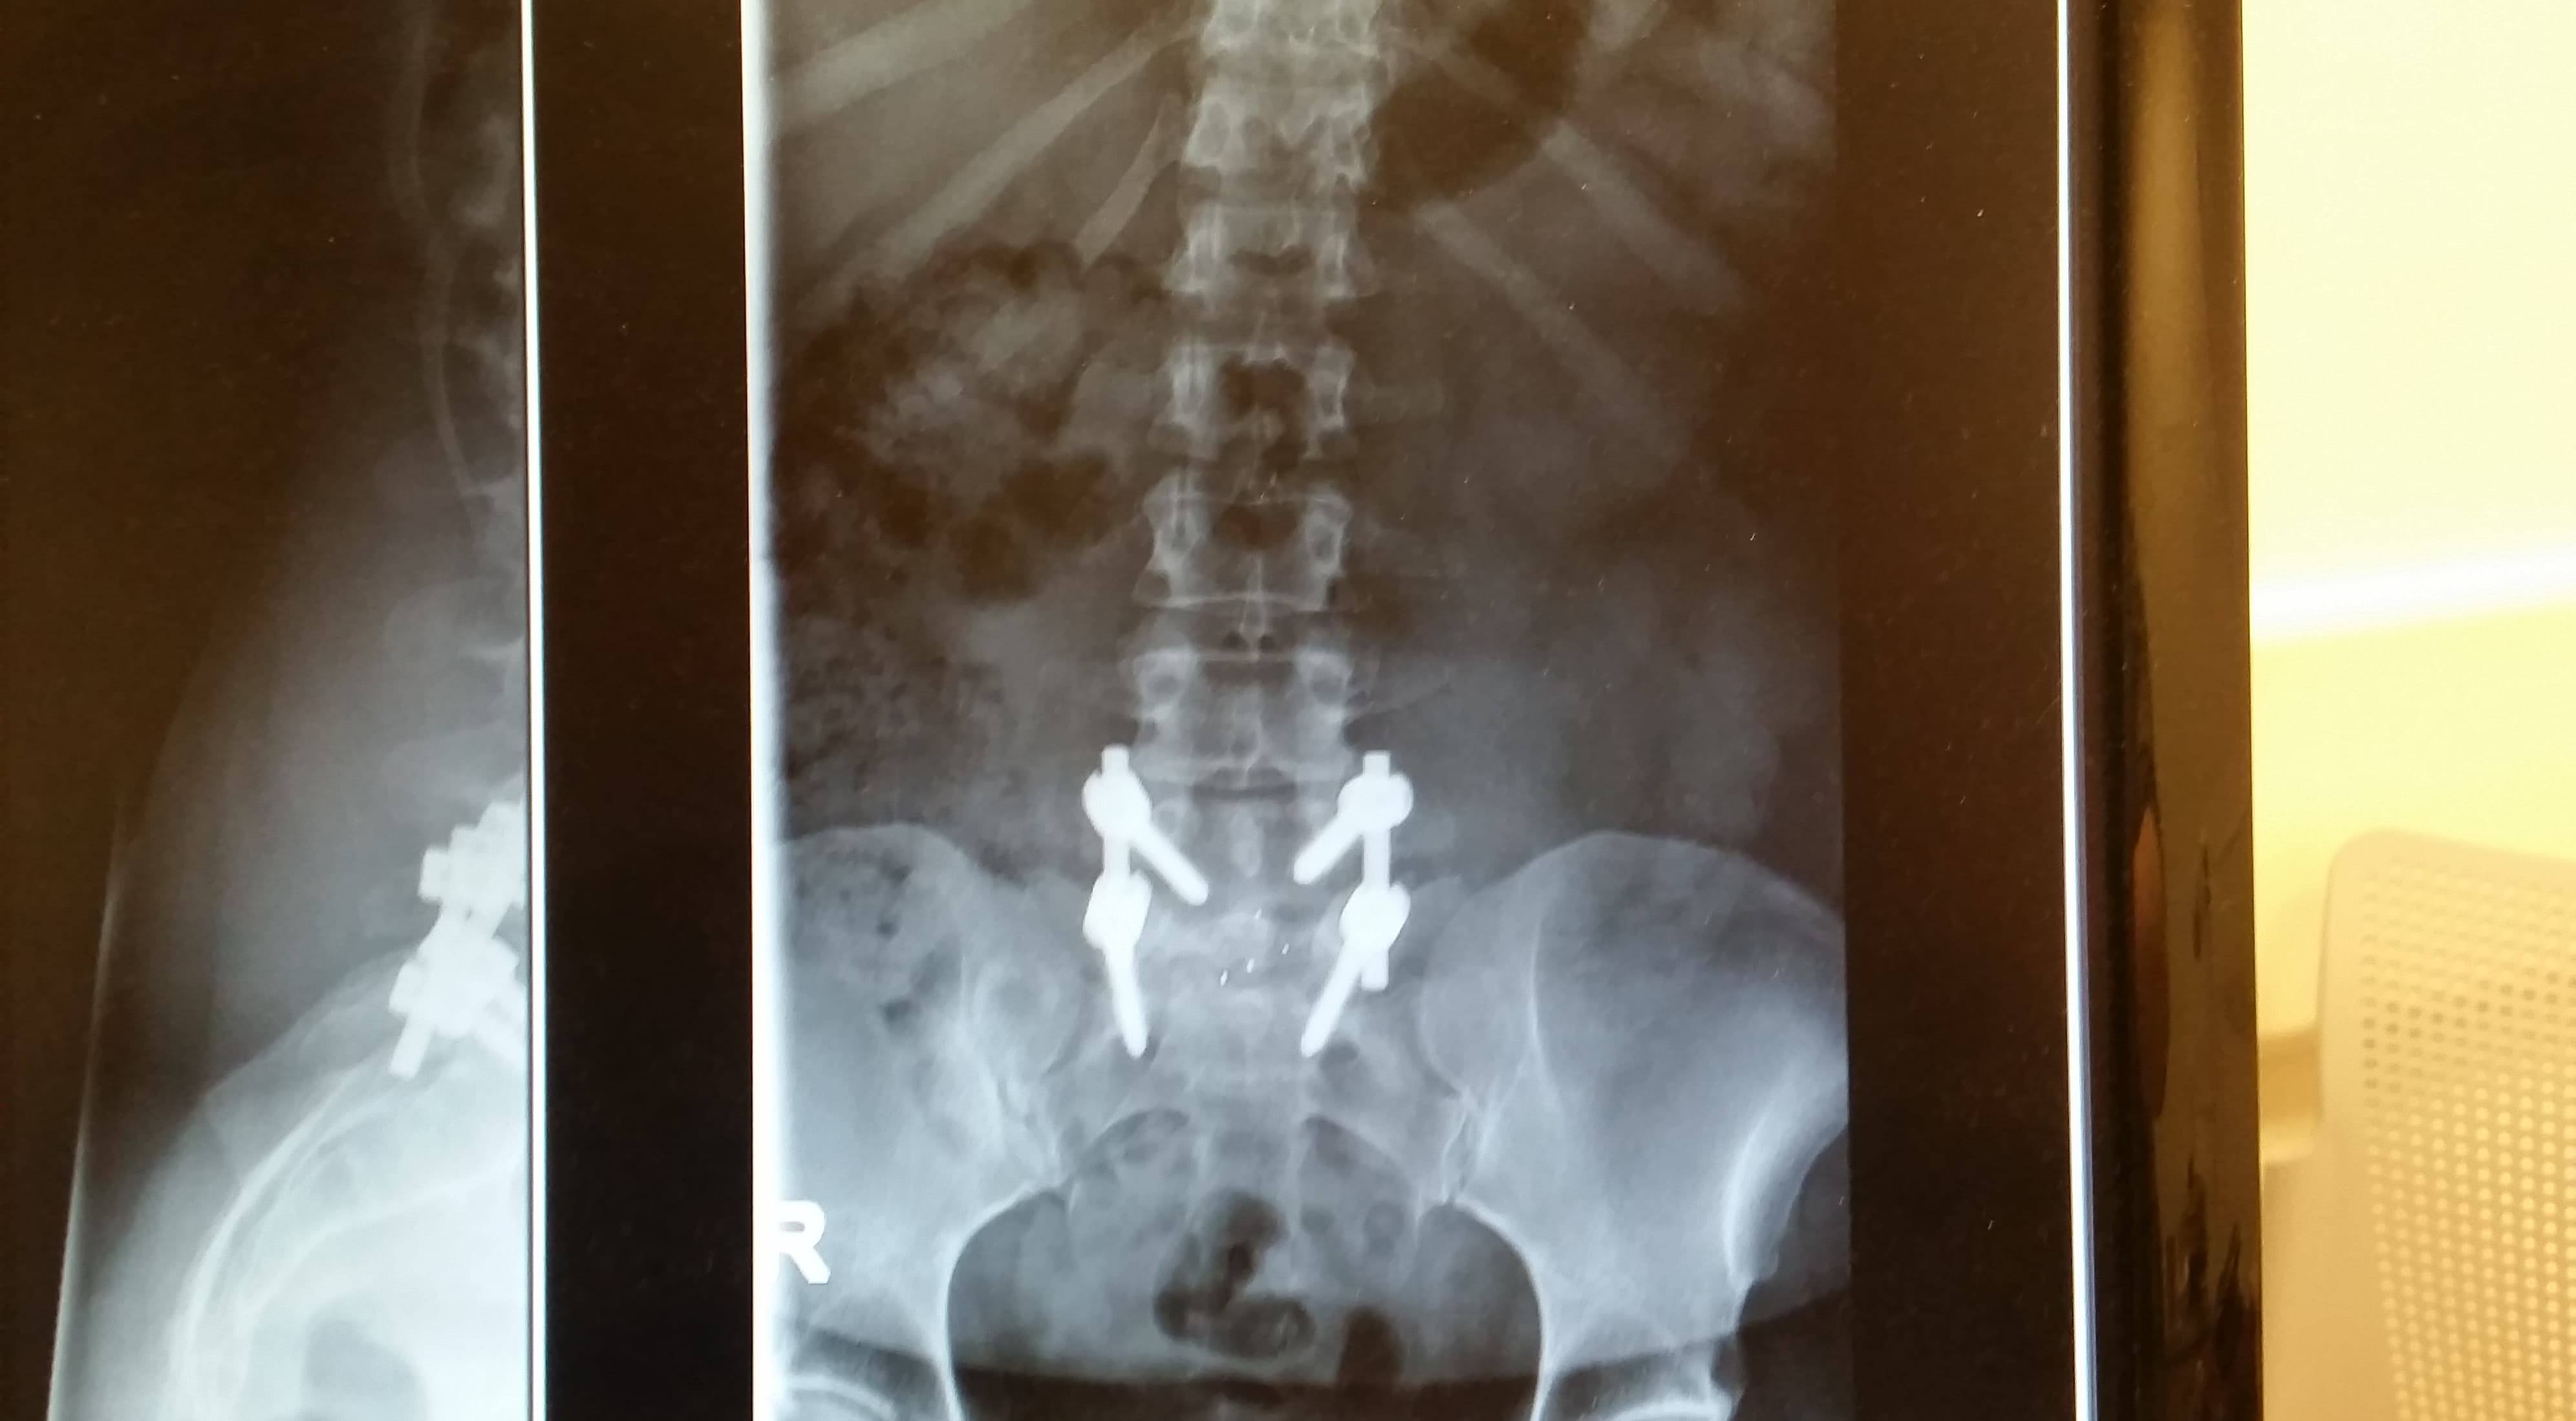

By 10 years, 18 patients required revision, and by 15 years, 24 patients required revision. Recovery from this spine surgery may include wearing a spinal brace and several months of restricted activity to ensure a successful surgical outcome. And approximately 96% with primary fusion get to enjoy the life after spinal fusion same as before.

And you may lose some flexibility permanently. At any point after surgery, there is the risk of hardware failure such as rods breaking or screws coming loose. the body is stressed by the effects of anesthesia and surgery.

Out of 73 patients, five years after surgery, seven patients required revision. The term failed back surgery syndrome has been used to describe continued or persistent pain after previous back surgeries. It has been 2 years since my back surgery.